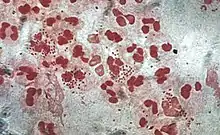

Pus under a microscope, there are many white blood cells with lobed nuclei. Inside some of the cells there are hundreds of bacteria that have been engulfed.

Micrograph of Gram-stained pus showing Neisseria gonorrhoeae bacteria inside phagocytes and their relative sizes